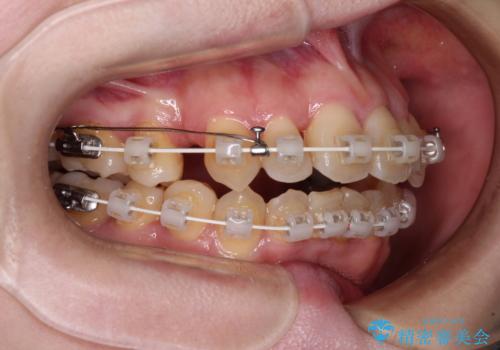

舌の突出癖が強く、治療途中で上下前歯が乖離した開咬となってしまいました。

舌のトレーニングで開咬は改善できますが、なかなかトレーニングが進まず、治療期間は想定よりも長期化してしまいました。